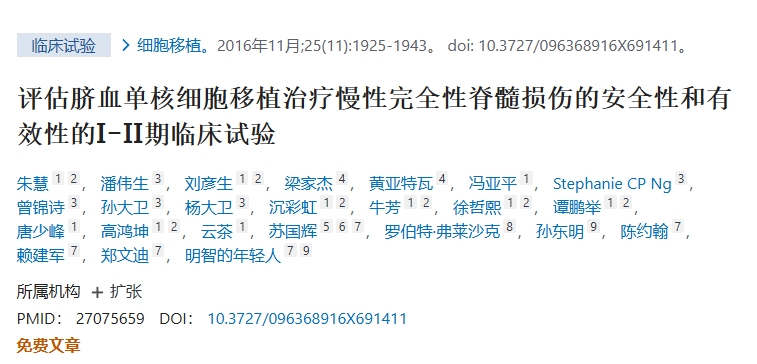

在一項利用臍帶血單核細胞的研究中,Zhu等人向脊髓注入了五種不同劑量的細胞:160萬個細胞、320萬個細胞和640萬個細胞。

2016年,朱教授及其同事報道了將臍帶血骨髓單核細胞注射到脊髓治療慢性脊髓損傷的結果,其中包括香港的8名患者和昆明的20名患者。

雖然香港的8名患者的運動功能、脊髓損傷步行指數 (WISCI) 和脊髓獨立性測量 (SCIM) 評分沒有變化,但昆明的20名患者的WISCI和SCIM評分均有所改善。手術前,只有2名患者在協助下行走10米,并且術前不需要協助進行膀胱或腸道管理。

細胞治療后約一年,WISCI和SCIM評分有所改善:20名患者中有15名行走10米(p=0.001),20名患者中有12名不需要協助進行膀胱管理(p=0.001)或腸道管理(p=0.002)。5名患者從完全性SCI轉為不完全性SCI(2名感覺 SCI,3名運動性SCI;p=0.038)。